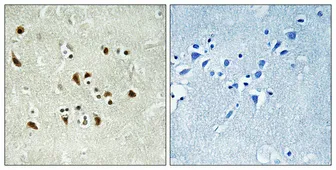

GFAP Rabbit Polyclonal Antibody

Cat: APRab11410